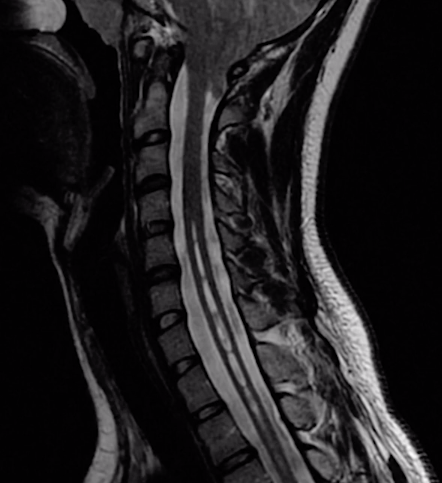

Mujer que presenta pérdida de termoalgesia en las EESS pero no en las EEII. Se ha hecho quemaduras sin darse cuenta

A

Siringomielia

Qué clinica provoca la siringomiélia

Sd medular central: No termoalgesia ( solo a nivel lesión ) : disociación Paresia, arreflexia segmentária ( 2a MT ) Horner IL, paralisis espastica inf ( 1a MT ) No sensibilidad profunda